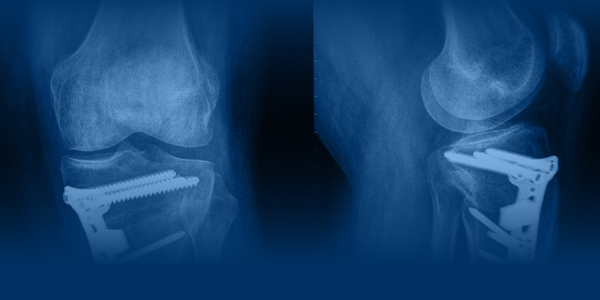

MAKE OSTEOTOMY

GREAT AGAIN

Osteotomy around the knee is rapidly evolving and reclaiming its rightful place in modern orthopaedics. With improved techniques and a strong focus on joint preservation, mastering osteotomy is no longer optional - it is essential.

This intensive 2-day workshop is designed to simplify osteotomy, remove uncertainties, and empower surgeons with clarity and confidence.

Cover the following surgical procedures in the form of live demonstrations, and hands on practise Medial Opening HTO | Medial Closing DFO | TTO Approach to lateral DFO | Approach to lateral closing HTO Slope Correction Osteotomy (Demonstration Only)